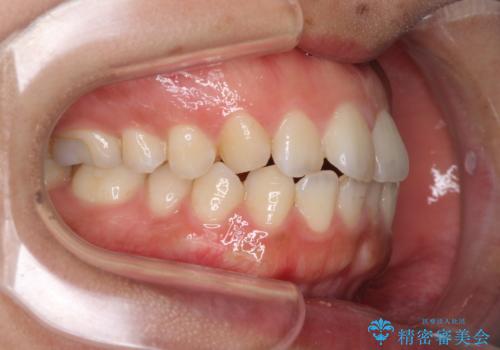

全く目立たないワイヤー矯正 上下リンガル矯正

- 上下の前歯のでこぼこを気にして来院された患者様です。

結婚式が近いこともあり、全く目立たない裏側矯正により口元を整えることとしました。

下顎が左側にずれているため、裏側矯正ということもあり咬み合わせを整えるのに時間がかかってしまいました。